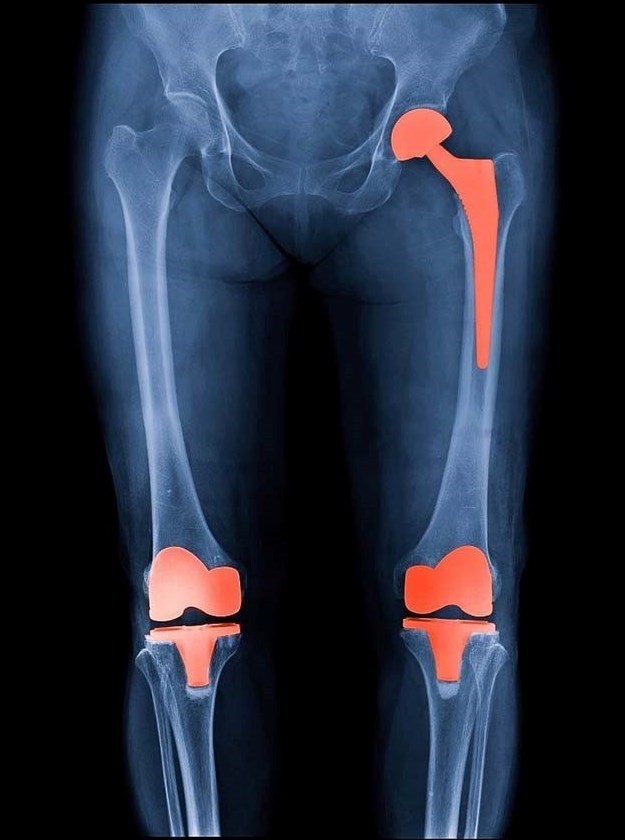

زاویه چرخش دیستال فمور با سی تی اسکن سه بعدی در جراحیهای زانو

سی تی اسکن سه بعدی به عنوان دقیق ترین استاندارد طلایی برای ارزیابی آناتومی پیچیده استخوان فمور در جراحی تعویض مفصل زانو شناخته می شود. در جراحی های بازسازی زانو، تعیین دقیق زاویه چرخش دیستال فمور نه تنها بر پایداری مفصل تاثیر می گذارد، بلکه عامل اصلی در جلوگیری از دردهای مزمن پس از عمل […]